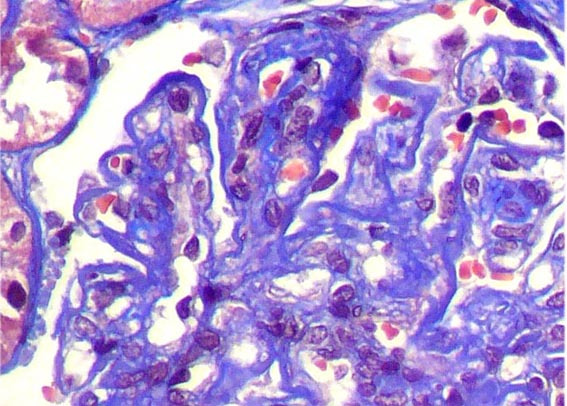

Figura 6.

Plata-metenamina, X400.

Figura 7.

El mismo glomérulo de la imagen anterior, amplificada. Plata-metenamina,

X400.